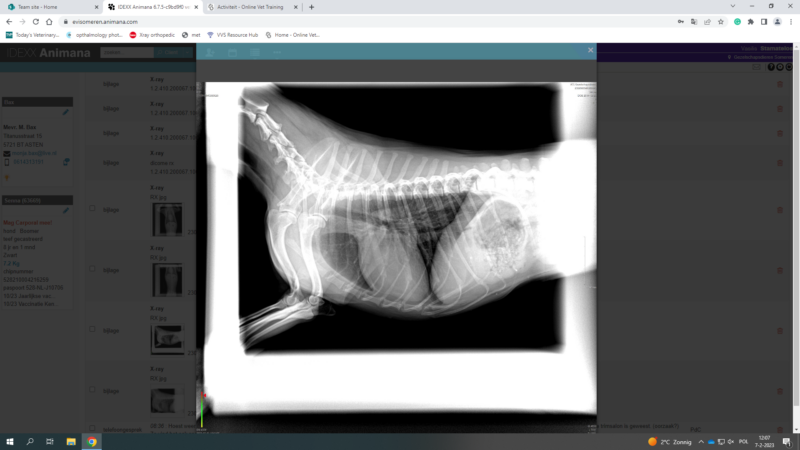

these are the photos of the bloodwork and from the ultrasound

This post is about a patient of mine that came to me on Wednesday.

General information and history: Cat, male, not castrated, 11 years old with different behaviour since 3 days. According with the owners, the cat didnt want to eat and drink for 3 days. Also he wasnt active and he was hiding. The owners didnt have…

Chronic Cough problem with underline heart disease?

i upload this post in order to discuss one of my cases with you

Its about a yorkshire terrier, 3 years old, female, sterilised, that has coughing problems for 6 months. According with the owner, the problem didnt start 6 months ago, but earlier. But the last 6 months is really getting worse. Before it was once per week…